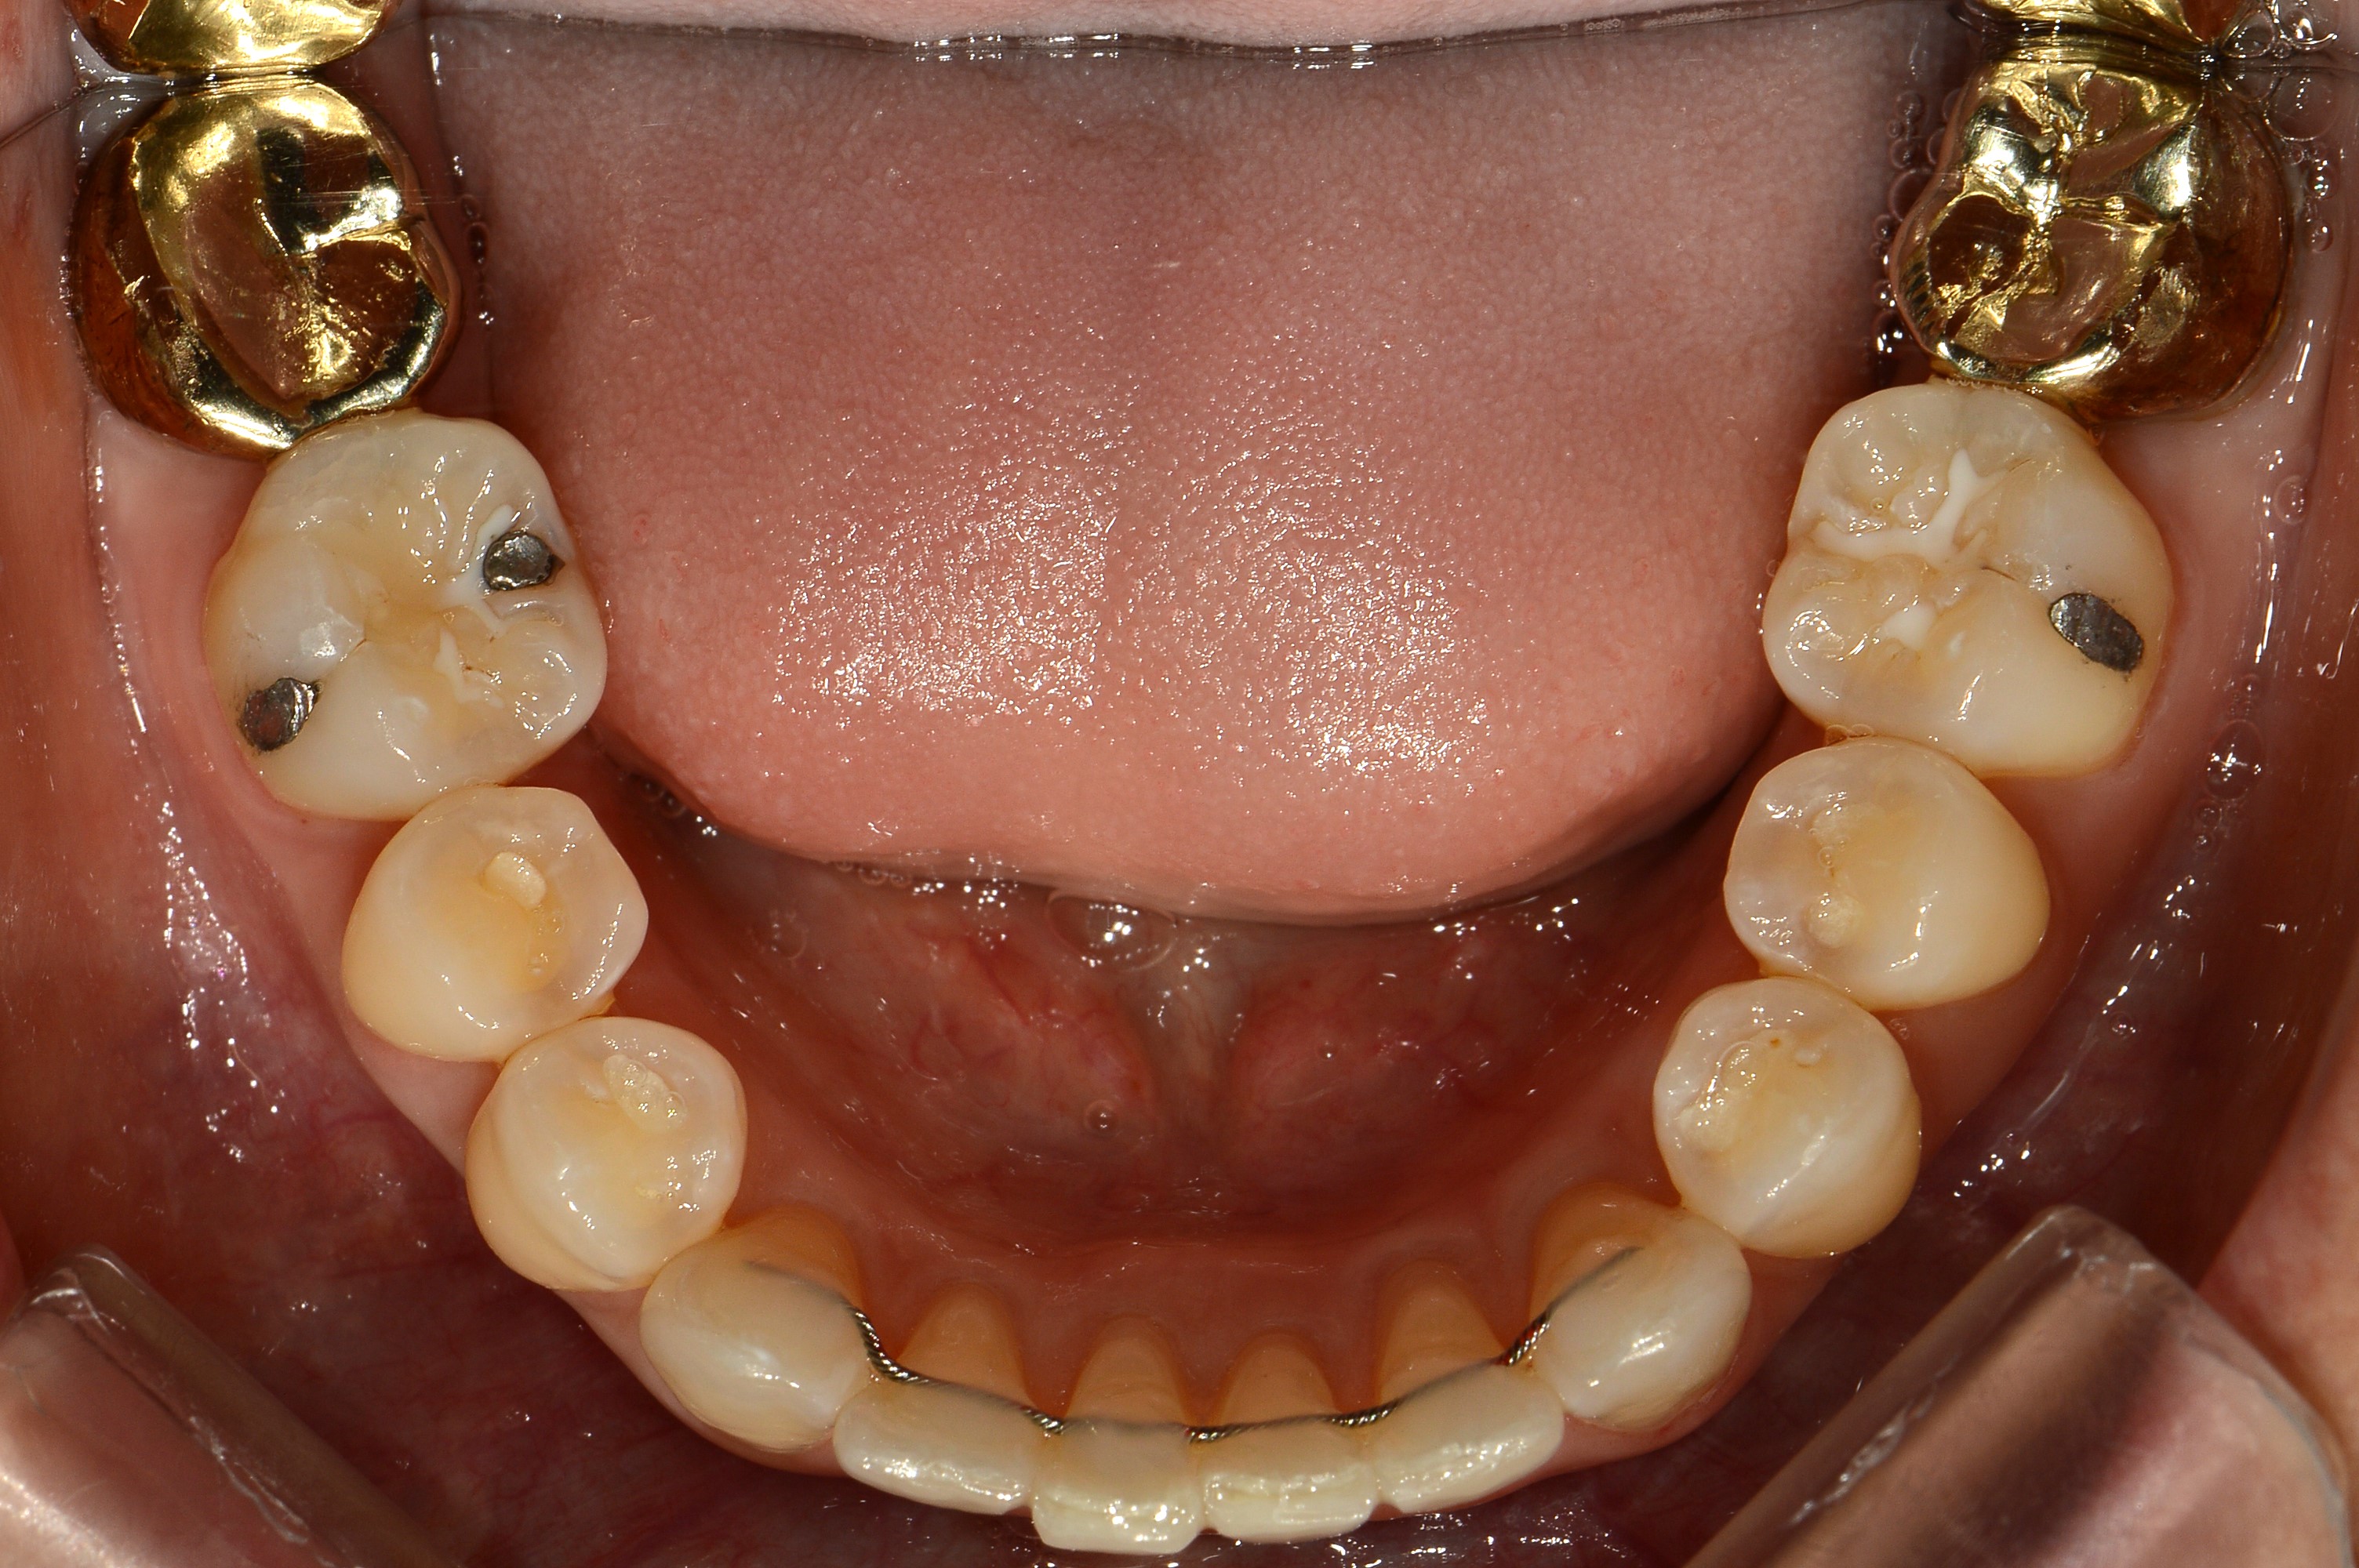

치료 전 사진입니다.